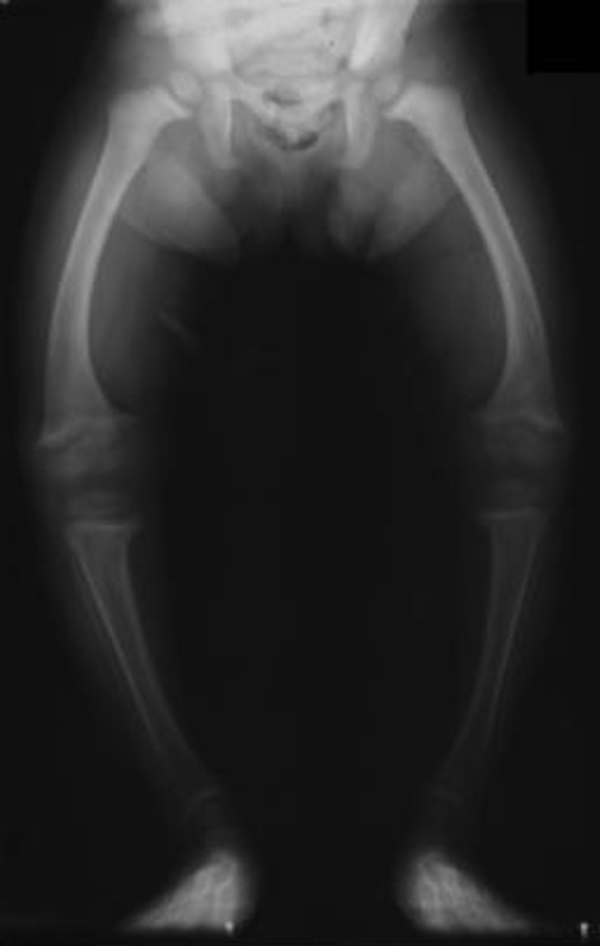

• ↑Ca++ excretion : 2° hyperparathyroidism, nephrocalcinosis, renal stones

• Vit-D deficiency : osteomalacia, ricketts